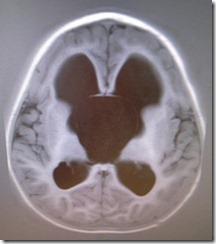

Figure: Normal brain MRI cross section.

This normal scan shows the spaces in the middle of the brain that contain and produce the Cerebrospinal fluid.

This fluid is needed by the brain but is drained in the middle down the spinal column.